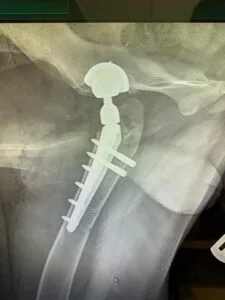

В 2021-2022 гг. — с соавторами разработал и запатентовал собственную систему для протезирования тазобедренного сустава V@Art (Виарт — https://v-art.info ). Данной системой пользуются ведущие врачи в России, а также в Белоруссии, Израиле, Кипре, Китае и Индии.

В 2022 — 2023 годах оформил три патента на протез тазобедренного сустава; на костную пластину; метод динамической стабилизации пояснично-крестцового отдела позвоночного столба у собак.

В 2016 году совместно со Слободаном Тепичем и Ильей Владимировичем Средой — впервые в России провел несколько операций по эндопротезированию тазобедренного сустава безцементным эндопротезом компании KYON.

На 2020 год выполнил с коллегами больше всех в России операций по эндопротезированию тазобедренных суставов-операция, которая позволяет полностью восстановить опорную функцию тазовых конечностей у собак средних, больших и гигантских пород;